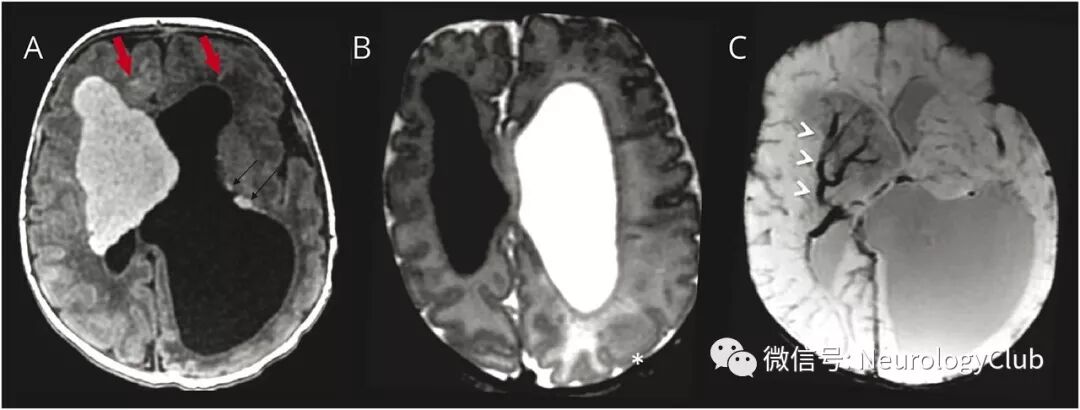

9天大女婴,在产前超声检查中发现脑部和心脏病灶,怀疑结节性硬化症。本例患者头颅MRI可见以Monro孔(孟氏孔)为中心的一巨大的脑室内和脑实质内肿块,有不典型的影像学表现:均匀的T1高信号和T2低信号(图1A-B),可能与稀少的髓鞘形成有关;SWI上可见明显的静脉引流(图1C);ADC呈低信号,符合T2暗化效应(blackout effect)(图2A-B)。MRS可见胆碱和肌醇峰升高(图2C)。这些发现符合新生儿室管膜下巨大星形细胞瘤。室管膜下结节,皮质结节和辐射带也呈不典型的T1高信号和T2低信号(图1A-B)。

(图1:室管膜下巨大星形细胞瘤:A:T1高信号;B:T2低信号;C:SWI可见明显的静脉引流[箭头];室管膜下结节:A:T1低信号[黑箭];辐射带:A:T1低信号[红箭];皮质结节:B:T2低信号[*])